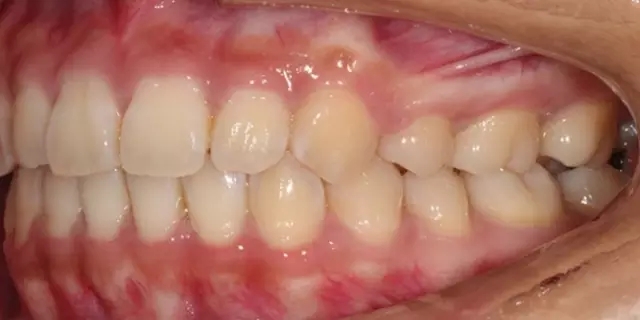

Damon 病例分享:安氏 II 類(lèi)二分類(lèi)露齦笑的矯治(董一磊)

患者信息

治療前后對(duì)比